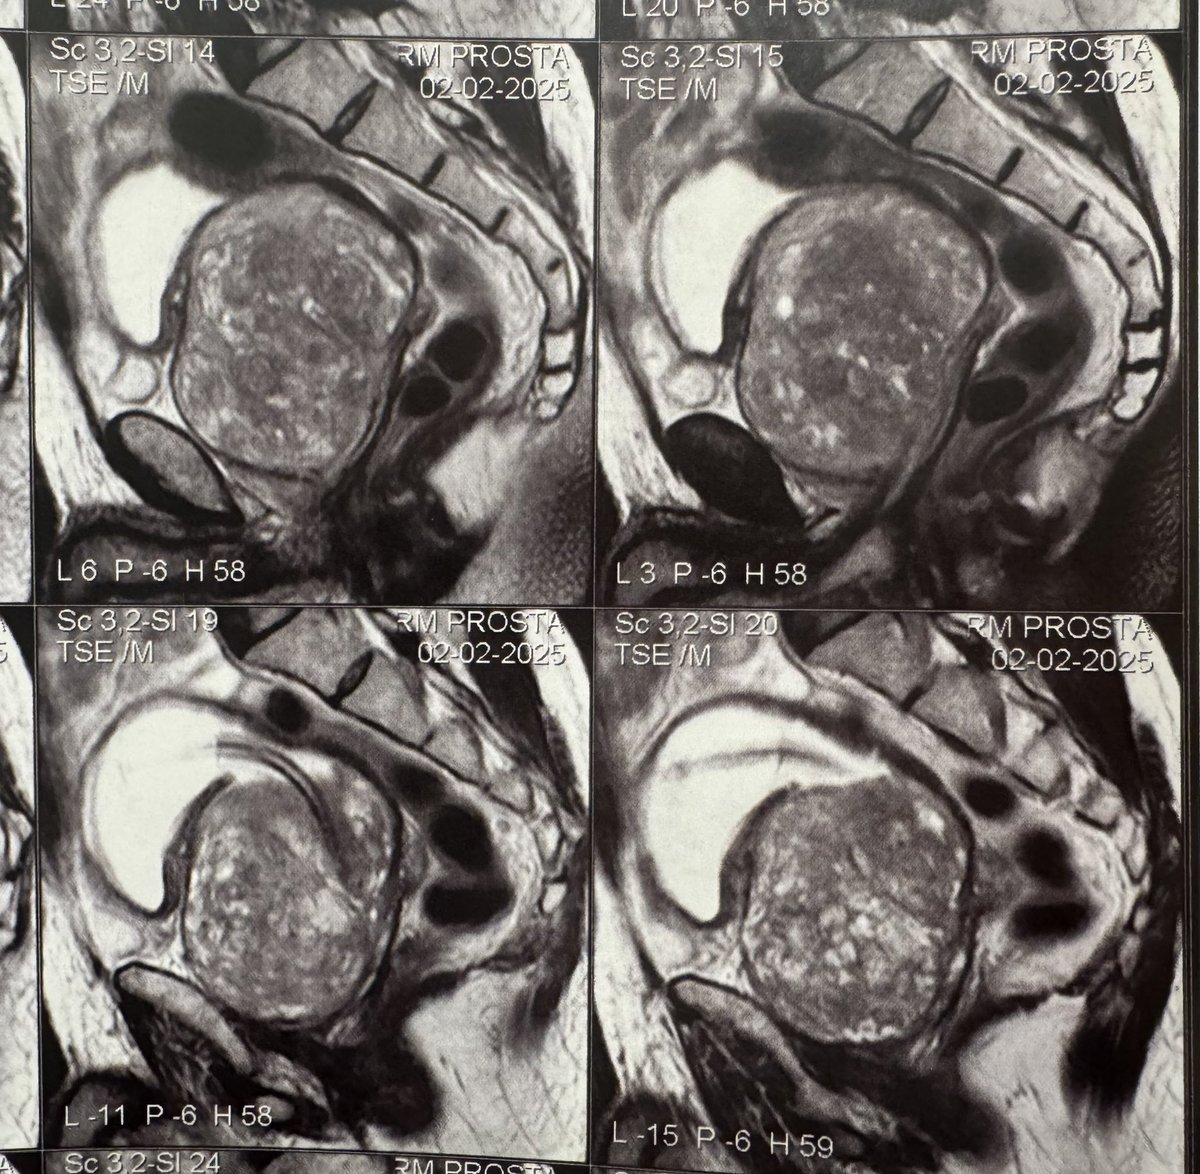

BPH case of the week: 68y, severe LUTS, AUR and chronic catheter since July/2023 Jehovah's Witness (no 🩸 allowed) MRI: 332g, PIRADS 2 What would be your approach? - Open - RASP - HoLEP/EEP 26F - MiLEP 22F Please share your comments below!

Follow up🧵 He lives in Angola, Africa and visited many urologists that unanimously told him about a high risk of transfusion in such a large gland. All doctors demanded informed consent for transfusion, which is very difficult for them to sign due to their religious beliefs /1